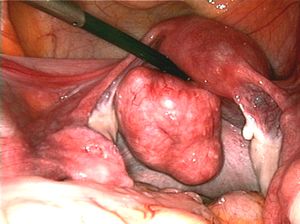

| Uterine fibroids as seen during laparoscopic surgery | |

Myomectomy

Myomectomy is a surgery to remove one or more fibroids. It is usually recommended when more conservative treatment options fail for women who want fertility preserving surgery or who want to retain the uterus.[60]

- A laparoscopic myomectomy is done through a small incision near the navel. The physician uses a laparoscope and surgical instruments to remove the fibroids. Studies have suggested that laparoscopic myomectomy leads to lower morbidity rates and faster recovery than does laparotomic myomectomy.[61]